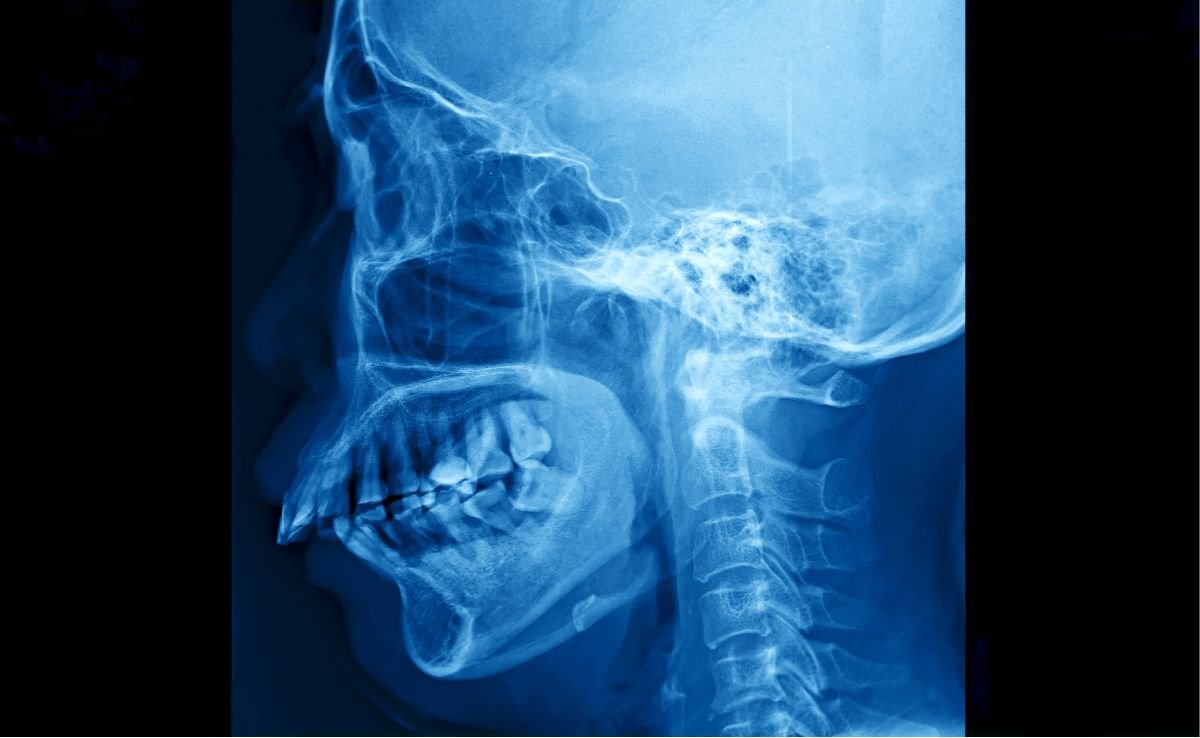

The process starts with undergoing digital imaging such as X-rays or CBCT scans, which help evaluate the condition of your teeth, jawbone, and soft tissues. The surgeon then creates a personalised treatment plan, explains the procedure, and addresses any concerns or risks.

Yes, certain maxillofacial procedures, such as jaw advancement surgery (orthognathic surgery), can improve or resolve obstructive sleep apnea by widening the airway. This is typically considered when other non-surgical treatments like CPAP fail. Your oral surgeon will evaluate your condition and refer you for a sleep study if necessary.